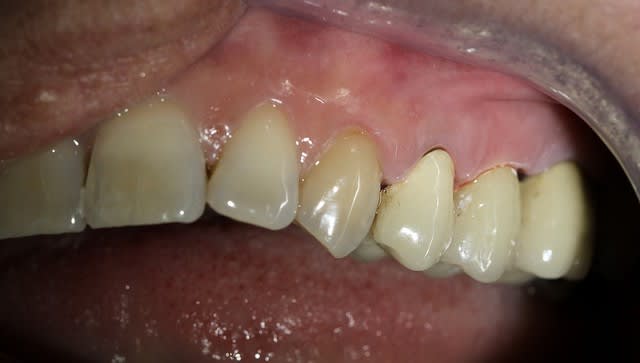

Voici un cas moins gentil avec élimination de la cause du problème pour reprendre les termes de Marc.

Il s'agit d'une patiente de 90 ans sur qui je reconstituais les secteurs postérieurs mandibulaires, ce qui fera l'objet d'un prochain post d'ailleurs, et dont un simple détartrage révélait la présence d'une énorme carie sous le pilier distal d'un bridge reliant la 23 à la 26.

Ayant intérêt à éviter de commencer un gros chantier alors qu'un autre était en cours, j'ai opté pour dégager et éliminer cette carie en conservant provisoirement ce bridge qui tenait bien, avant de traiter ce secteur en tachant de récupérer la racine de la 26 si possible.